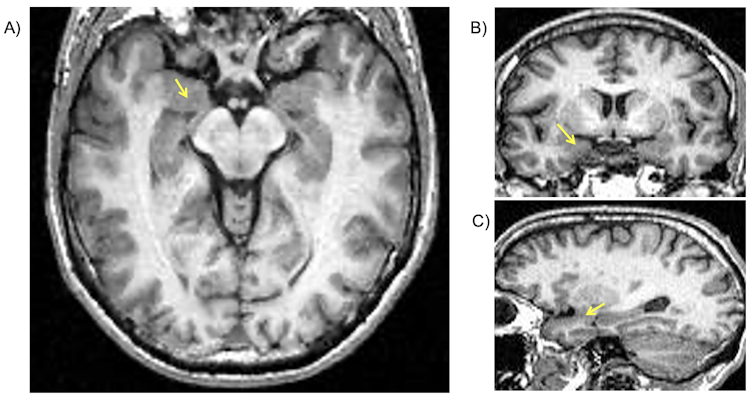

Localización de la amígdala en imágenes de resonancia magnética estructural (mostrada por las flechas amarillas). A) corte axial; B) corte coronal y c) corte sagital.